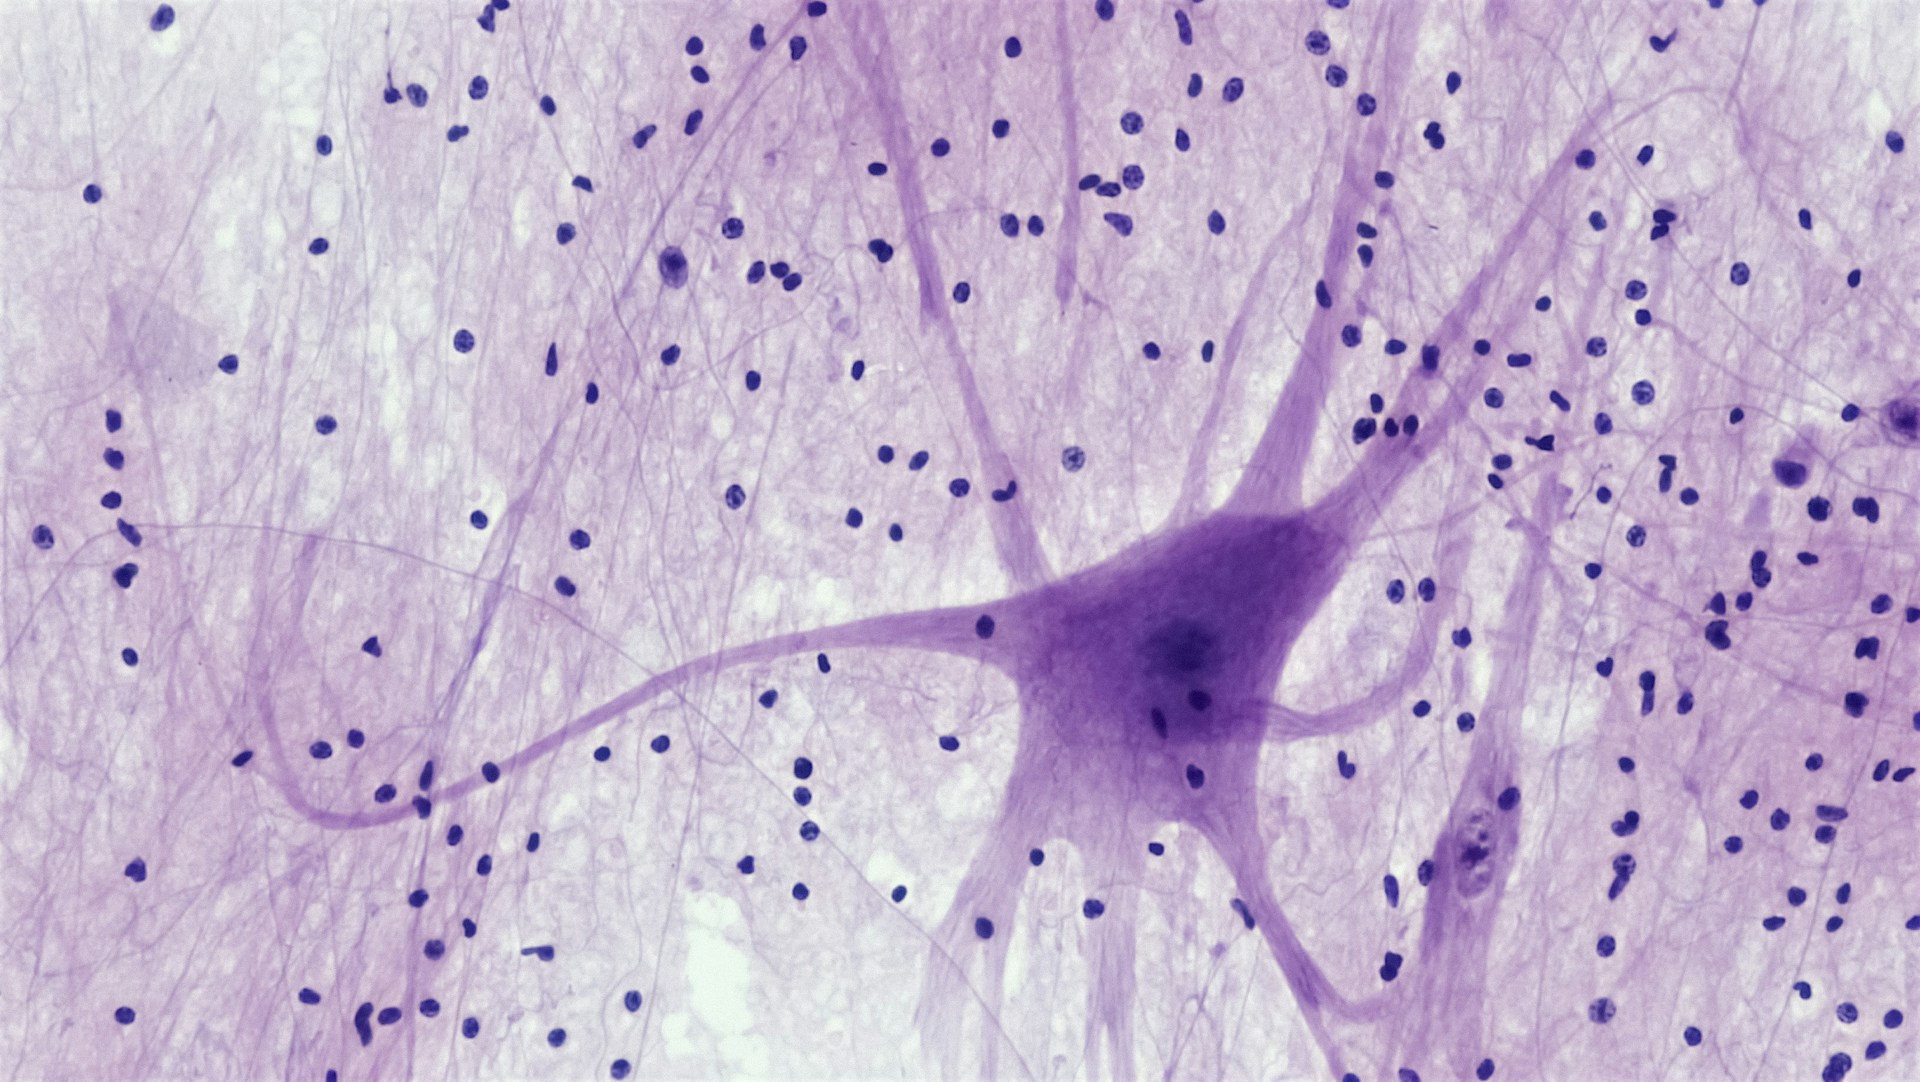

En la enfermedad de Huntington, una proteína tóxica generada por un gen defectuoso destruye de forma gradual las neuronas del cerebro, afectando funciones básicas como el movimiento, el habla y la estabilidad emocional.